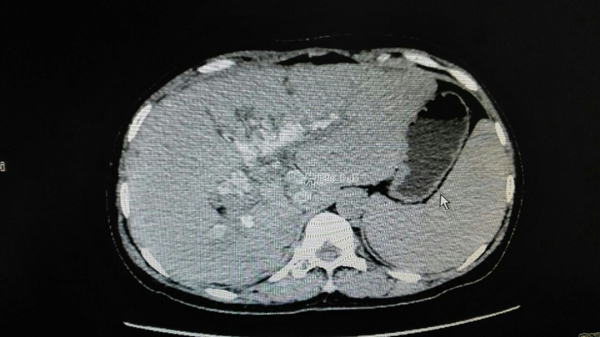

手术前胆囊中充满结石

手术后胆总管下端无结石